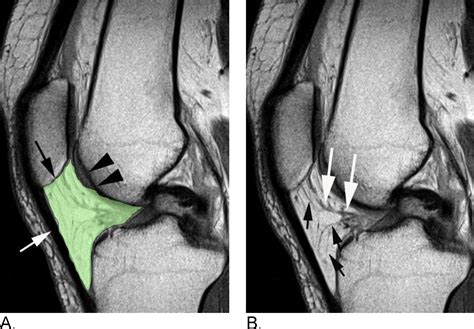

Hoffa’s Fat Pad, also known as the infrapatellar fat pad, is a specialized adipose tissue located in the anterior compartment of the knee. It is situated between the patellar tendon and the tibia, providing a protective layer that helps distribute forces and reduce wear and tear on the knee joint. The pad is richly innervated with sensory nerves, making it sensitive to pressure and movement.

Hoffa’s Syndrome

Hoffa’s Syndrome, also known as Hoffa’s Fat Pad Impingement, occurs when the fat pad becomes inflamed and swollen, often due to repetitive stress or trauma. This condition can cause anterior knee pain, tenderness, and swelling, particularly during activities that involve knee flexion and extension.

Fat Pad Impingement

Impingement of Hoffa’s Fat Pad can occur when the pad becomes trapped or compressed between the patellar tendon and the tibia. This can happen during activities that involve deep knee bending, such as squatting or lunging, and can cause anterior knee pain and stiffness.

In some cases, Hoffa’s Fat Pad can develop calcium deposits, a condition known as fat pad calcification. This can cause chronic pain and inflammation, and may require medical intervention to manage symptoms.